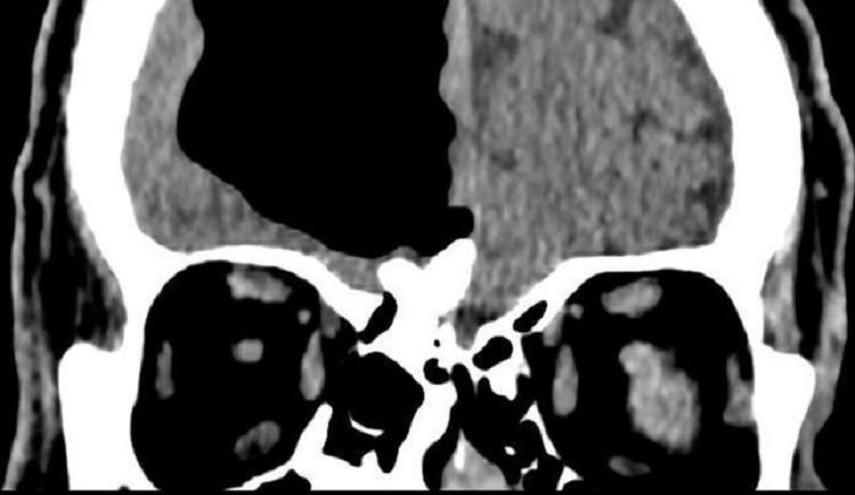

واكتشف الأطباء وجود "تجويف هوائي" يبلغ طوله 10 سنتيمترات في النصف الأيمن من دماغ رجل مسن نقل إلى المستشفى عقب شعوره بالدوار وسقوطه على الأرض، بعد أن تبددت شكوكهم بإصابته بسكتة دماغية.

وبينت نتائج التصوير بالرنين المغناطيسي لدماغ الرجل المسن، وجود ما يسمى بالفتق الهوائي وهو ما يلاحظ عادة لدى المرضى الذين يعانون من إصابات في أجزاء معيّنة من الجسم والأعضاء الداخلية.

كما كشف الفحص وجود ورم عظمي (تشكّل حميد في عظام الوجه يفصل بين تجويف الأنف والدماغ)، دخل من خلاله الهواء إلى دماغ الرجل وبقي فيه لعقود من الزمن، ما أدى إلى الضغط على الدماغ وتعطيل التنسيق في بعض وظائفه الحيوية. وهذا ما أدى إلى شكوى الرجل من الدوار المتكرر.